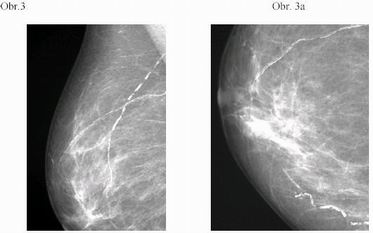

3. Pacientka M.M. 71 let. Mammografický obraz je doložen na

Obr. 3, Obr.3a.

Po provedené mammotomii histologicky verifikovaný invazivní

duktální karcinom, NOS varianta. Po operaci pT1c pN1b M0. Grade 3,

Estrogenní receptory 80%, progesteronové 75%, ki67 2%, Her2

negativní.

Otázkou je stanovení T klasifikace karcinomu, nebylo známo, jaká

porce karcinomu byla odstraněna mammotomií.